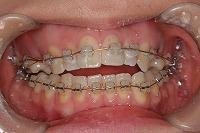

正面

上の前歯が出ている事を主訴に来院された、23歳2か月の女性です。診断「下顎骨の後方回転による骨格性上顎前突で開咬を伴う」上顎は両側第1小臼歯、下顎は抜歯をせず治療を行いました。